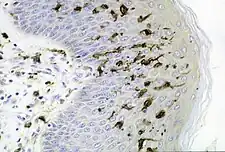

Células de Langerhans

Las células de Langerhans son un tipo de células dendríticas[46] que residen en la epidermis[47][48] contienen unos gránulos de gran tamaño llamados gránulos de Birbeck. Suelen encontrarse en los ganglios linfáticos y otros órganos, incluyendo el estrato espinoso de la epidermis. También se las puede encontrar en otras partes del cuerpo, especialmente en relación con la histiocitosis.[49]

Cuando se produce una infección de la piel, las células de Langerhans cercanas captan y procesan los antígenos. Las células de Langerhans derivan de la diferenciación celular de monocitos con el marcador Gr-1 (también conocido como Ly-6G/Ly-6C). La diferenciación requiere estimulación por el factor estimulador de colonias CSF-1.[50] Tienen una morfología y función similares a las de los macrófagos.[51] La proteína langerina, también presente en otras células dendríticas,[52] se encuentra en las células de Langerhans.[53] Investigaciones recientes apuntan a que esta proteína podría tener un papel especial en este tipo de células, haciendo de barrera natural para la transmisión del VIH-1 por células de Langerhans.[54] Uno de los investigadores apuntó que «la langerina es capaz de capturar virus del medio, previniendo así la infección», y que «como en general todos los tejidos exteriores del cuerpo tienen células de Langerhans, creemos que el cuerpo humano está dotado de un mecanismo de defensa antivírica que destruye los virus invasores».[55]